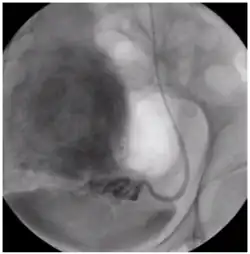

Восстановление кровотока в миоме через яичниковую артерию.